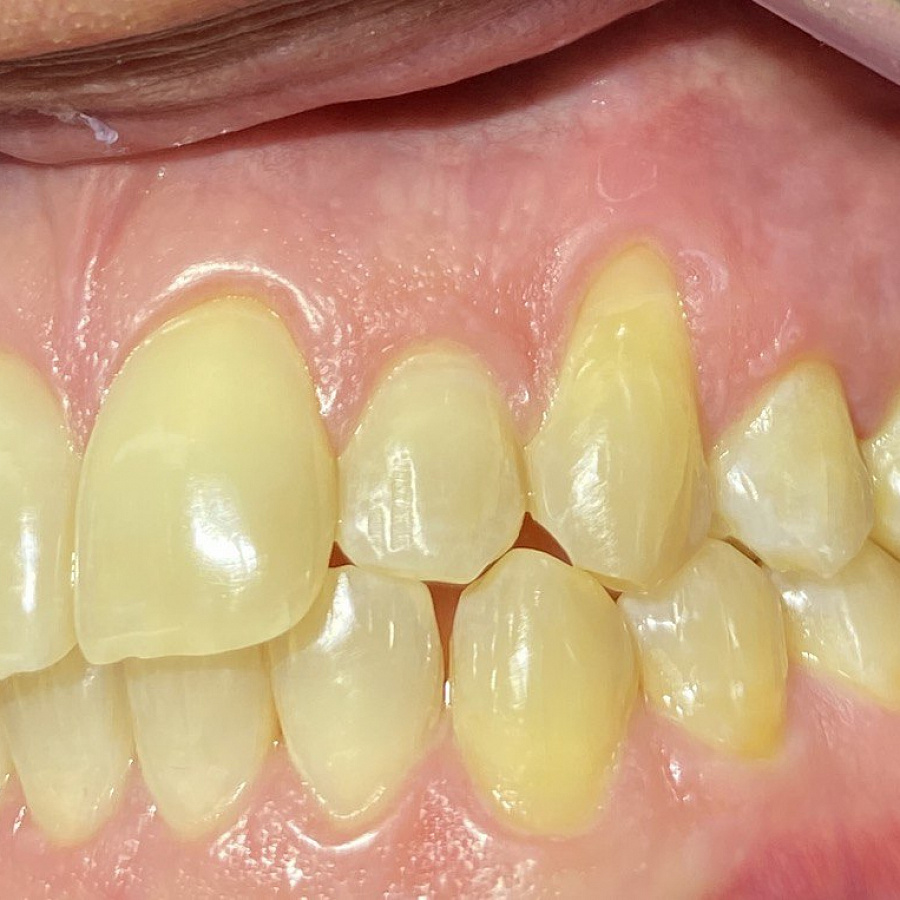

1. санация полости рта

2. ортодонтическое лечение с помощью элайнеров

3. восстановление плотных межзубных контактов с помощью ортопедических конструкций

4. виниры 12, 22 для удлинения резцов.

Ортодонтическое лечение с помощью элайнеров длилось 10 месяцев. Далее последовало протезирование и установка виниров.